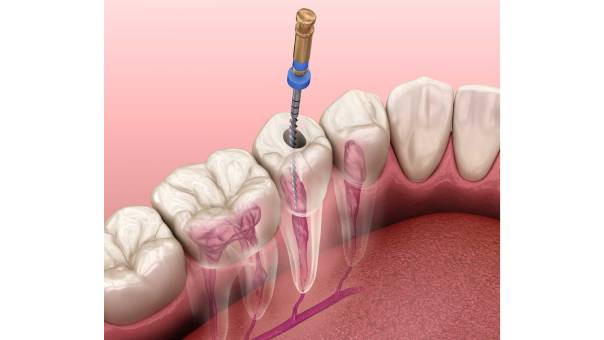

Locating the distal canal